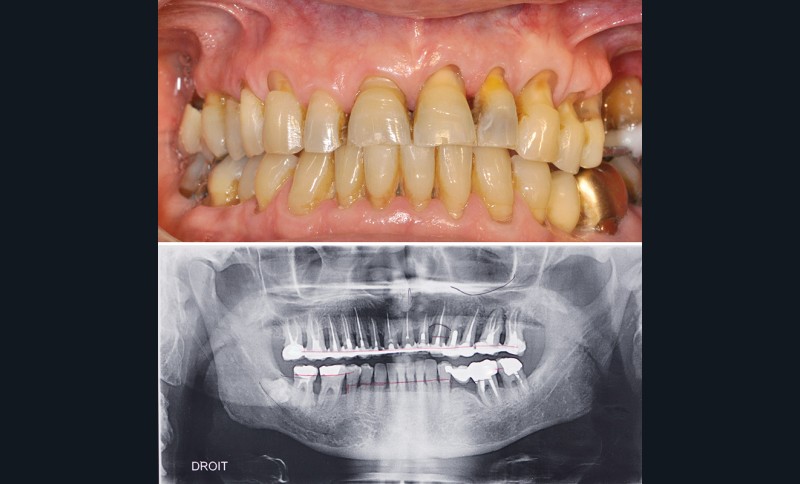

Avant de répondre aux différentes interrogations cliniques, il faut analyser la situation par des évaluations cliniques (état coronaire, situation endodontique, environnement parodontal) (fig. 1) puis, parfois, il est nécessaire de poursuivre cette étude préthérapeutique à l’aide d’outil de simulation comme l’articulateur (fig. 2), de techniques radiologiques en 3D. La conjugaison du recueil des informations et de l’analyse de la situation va nous permettre de proposer une solution en rapport avec la problématique médicale globale.

Ainsi, chez ce patient (fig. 3) quelle(s) solution(s) thérapeutique(s) peut-on envisager pour répondre au problème de mobilité dentaire en respectant son souhait de conservation ? Doit-on envisager d’extraire toutes les dents et d’avoir recours à une solution implantaire ou existe-t-il une solution fiable de conserver ses dents ?